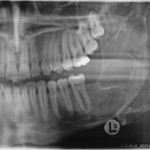

Attuali protocolli nel trattamento del tumore

Riassunto

La cheratocisti odontogena, dal 2005 classificata dall’Organizzazione Mondiale della Sanità come tumore odontogeno cheratosico, è una lesione benigna, localmente aggressiva, con un’alta tendenza alla recidiva. La...

Attuali protocolli nel trattamento del tumore odontogeno cheratosico (cheratocisti): revisione della letteratura

La cheratocisti odontogena, dal 2005 classificata dall’Organizzazione Mondiale della Sanità come tumore odontogeno cheratosico, è una lesione benigna, localmente aggressiva, con un’alta tendenza alla...